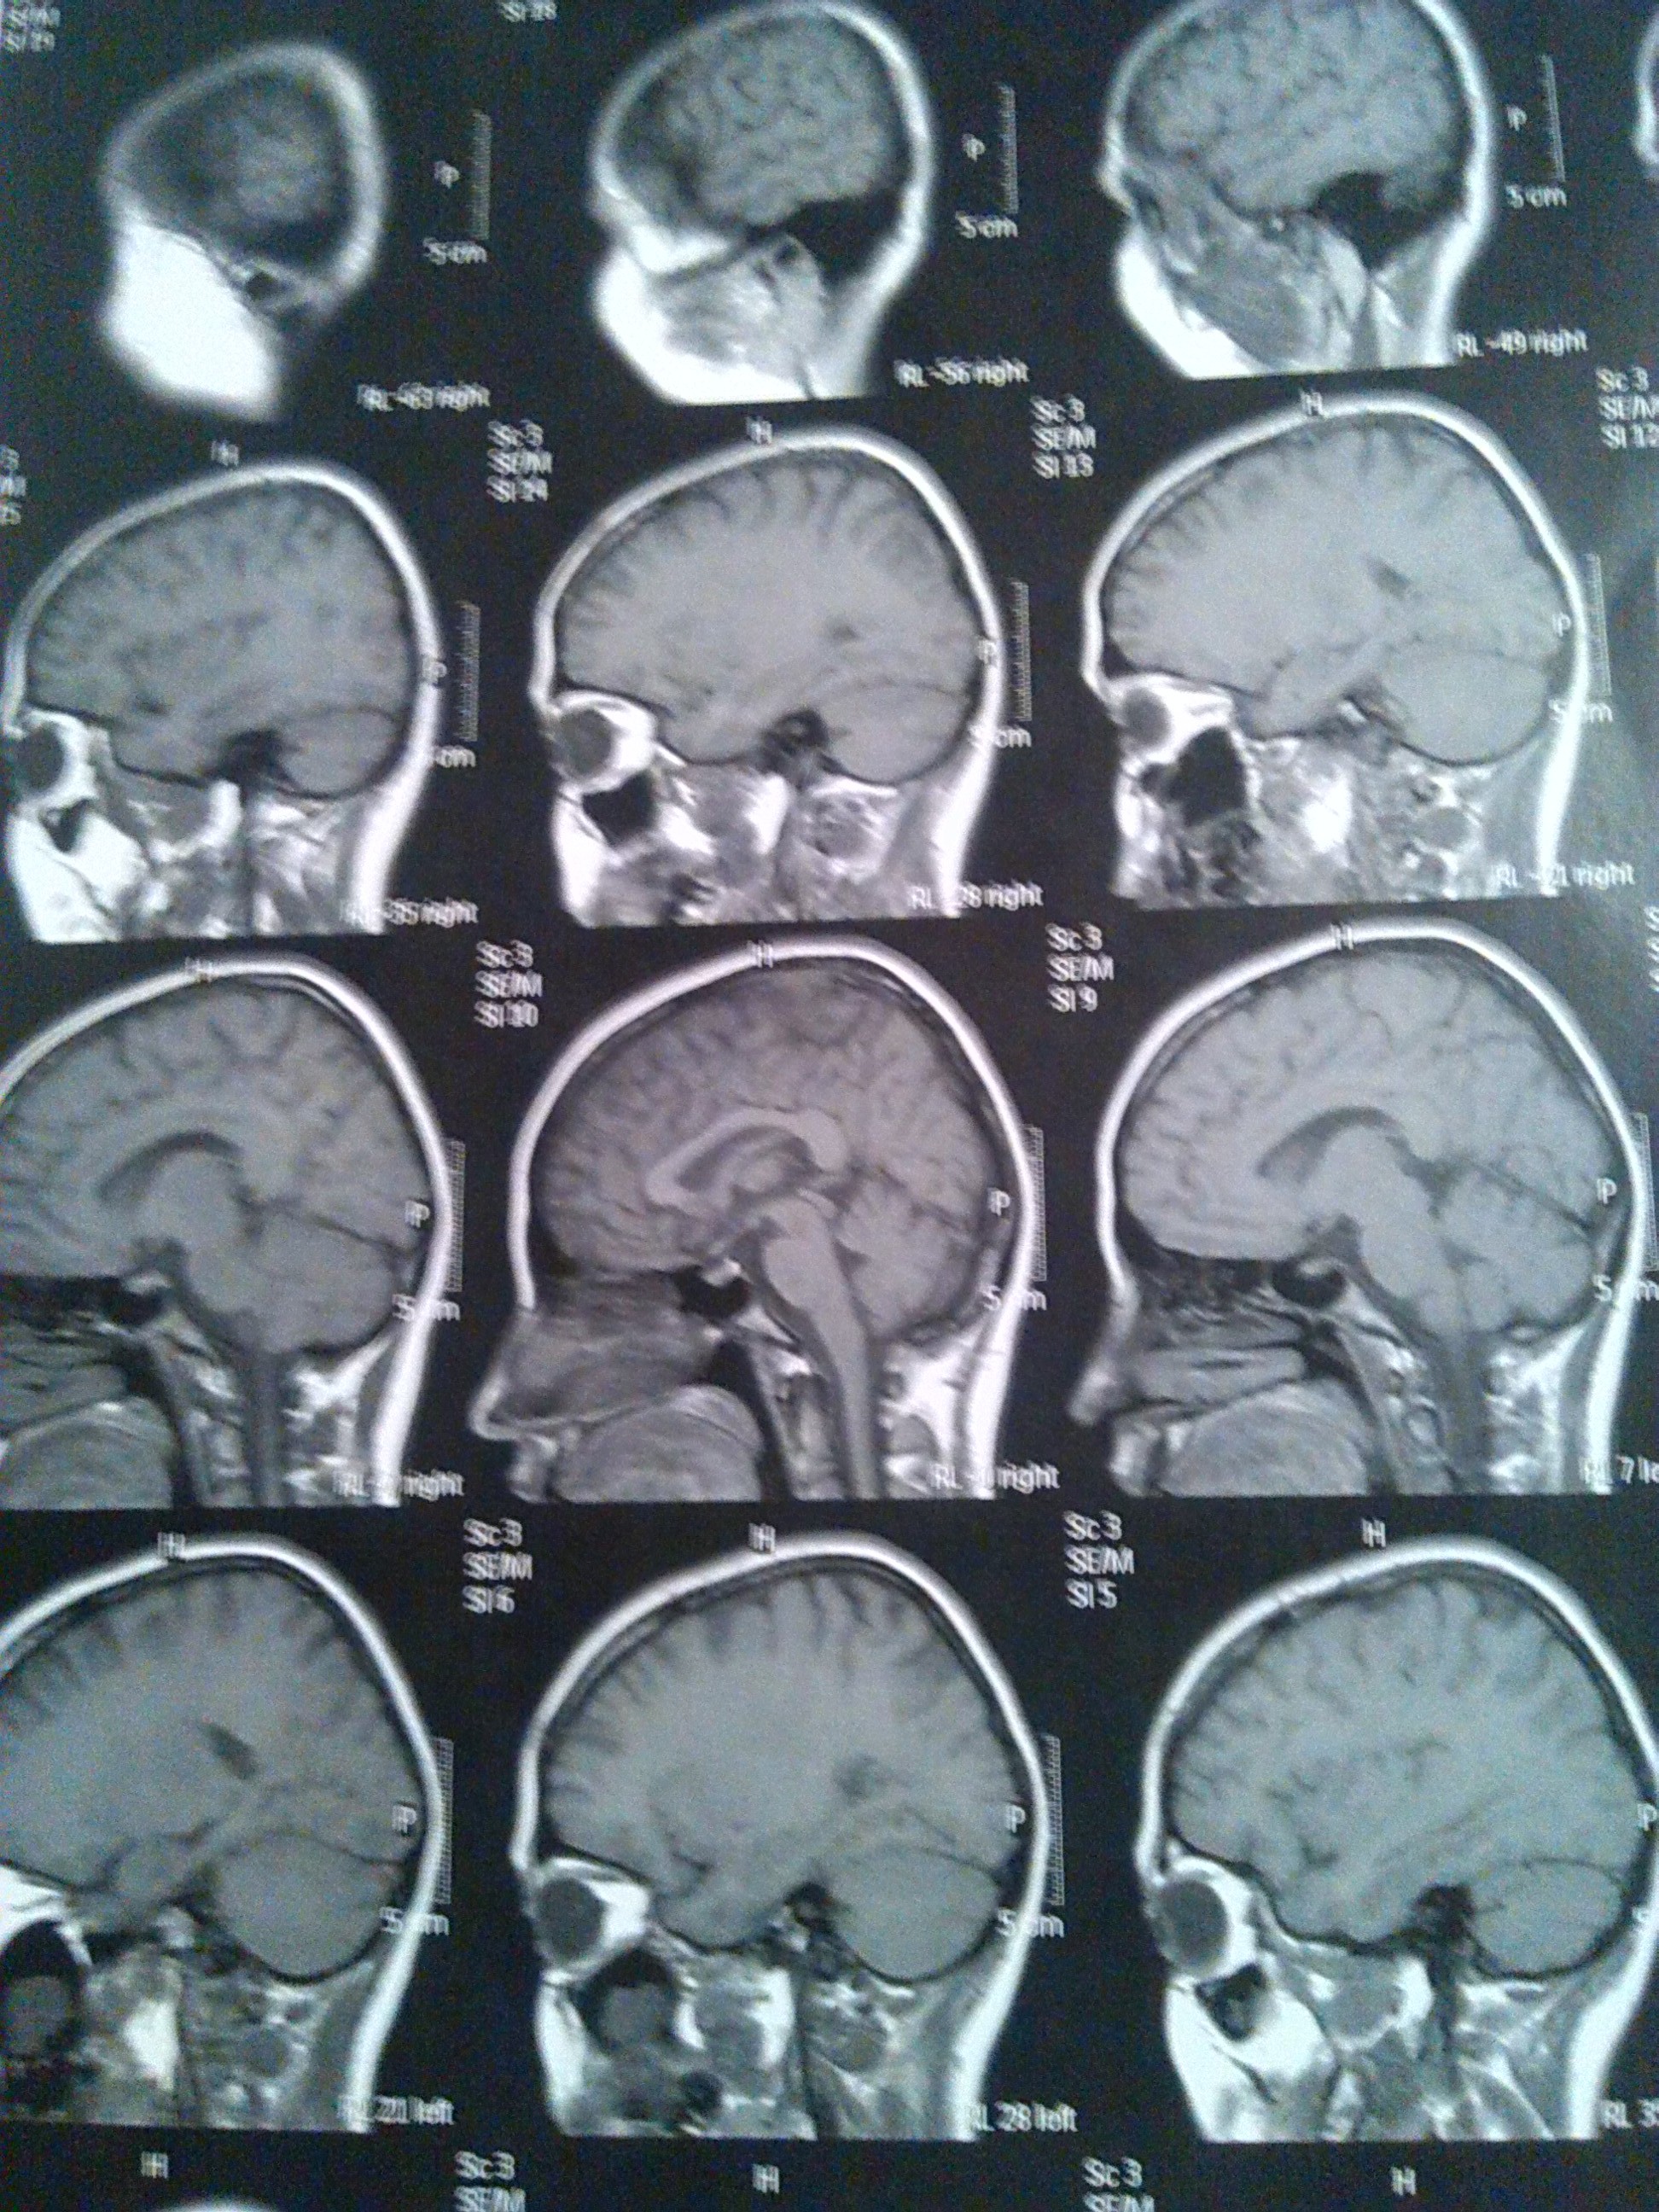

Es una enfermedad cerebral crónica caracterizada por episodios breves de contracciones musculares, llamadas convulsiones, a veces acompañada de la pérdida de la conciencia y del control de los músculos, dependiendo de la zona del cerebro en la que empieza el trastorno los ataques pueden variar. Estas convulsiones ocurren cuando las neuronas del cerebro envían señales erróneas, por lo que las personas empiezan a tener sensaciones y emociones desproporcionadas y no controladas[4].

Los pacientes con epilepsia sintomática, las causas pueden estar asociadas a daños cerebrales por lesiones antes del nacimiento como asfixia o traumatismos durante el parto y bajo peso al nacer, malformaciones congénitas, traumatismos craneoencefálicos graves, accidentes vasculares cerebrales, infecciones como meningitis y encefalitis, y/o tumores cerebrales.